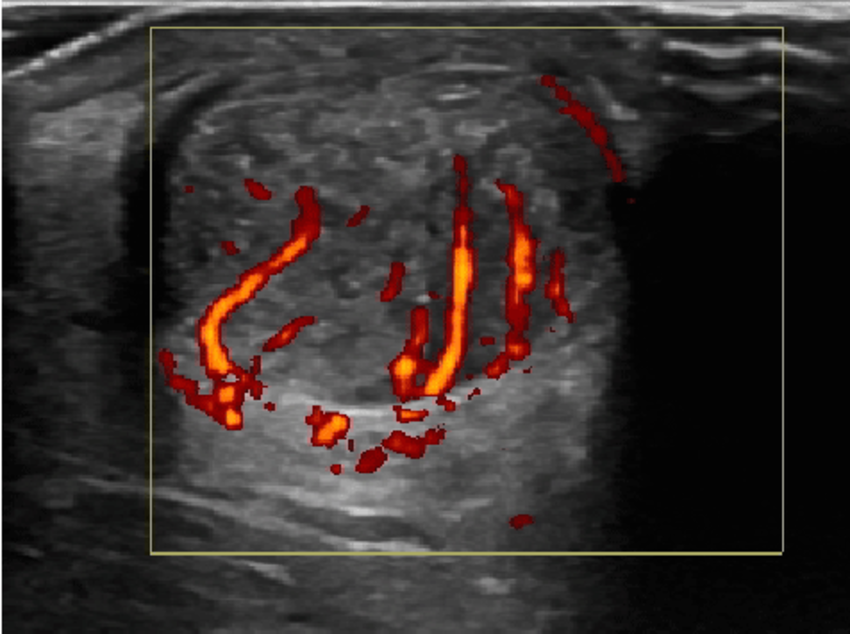

图:跟腱腱病超声横断面 + 多普勒血流信号

这张图展示了跟腱在超声横断面下的表现,有以下几个重点:

低回声区(暗区) 表示腱组织退变、胶原混乱,与慢性腱病的组织改变一致。

彩色多普勒高血流信号 指代新生血管/异常血流,是慢性病变活跃阶段的常见特征,提示代谢较活跃或“代偿性反应”。

这是最常见的慢性跟腱病类型,多见于跑步、跳跃人群。